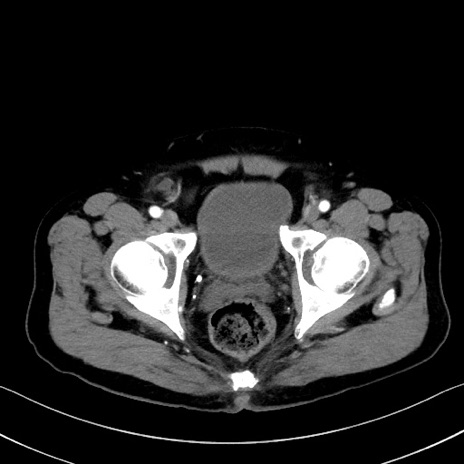

症例35(横断像)

冠状断像

【症例】70歳代 男性

【主訴】腹部膨満、嘔吐

【現病歴】昨日より腹部膨満感出現。本日増悪し、仙痛出現。嘔吐あり、受診。

【既往歴】糖尿病、胆摘後

【身体所見】BP 149/80mmHg、HR 74/min、BT 35.9℃、腹部:膨満、軟、圧痛なし。腸雑音減弱あり。上腹部正中切開瘢痕あり。

【データ】WBC 13500、CRP 1.72